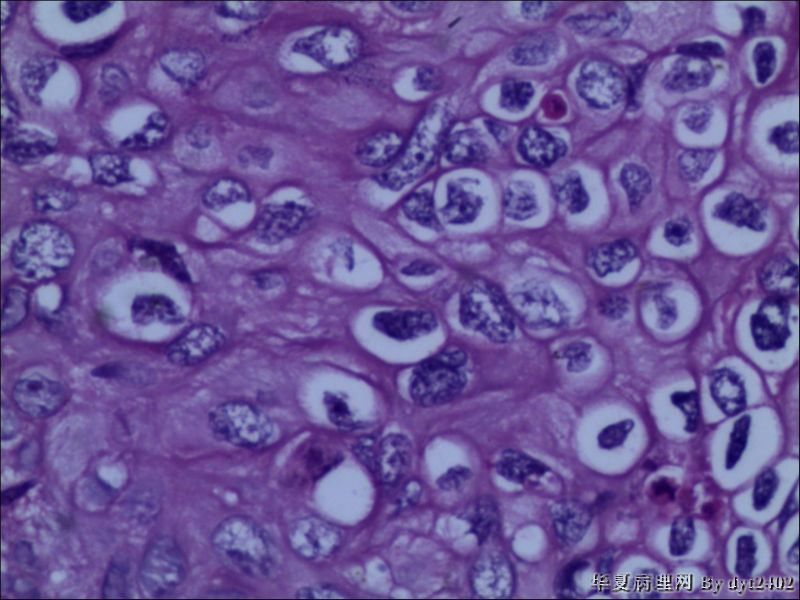

• 宫颈活检 其中一点较迷糊图1

图1

四点中三点是CIN iii,另一点怀疑有更重病变

这个病人是44岁,去年11月底阴道脱落细胞、TCT均见细胞异常,建议活检,病人犹豫,接着单位组织到外院体检时做阴道镜正常,后霉菌感染,此时宫颈未涂醋肉眼看还光滑,直至今年3月来做活检,事前做白带检查又见异常细胞,宫颈未涂醋见后上唇白上皮,涂醋酸后上下唇都有厚白上皮,镶嵌,夹活时上皮剥脱,未能夹到间质,阴道镜医生说至少有CIN III 到原位癌了。。镜下其中3点CIN III无疑,唯有9点处如6、7、11、14等所示结构,但我未见间质浸润,不能说是浸润癌,不知道有没基底细胞样鳞癌的可能,我发了个原位癌不除外深部有更重病变,。